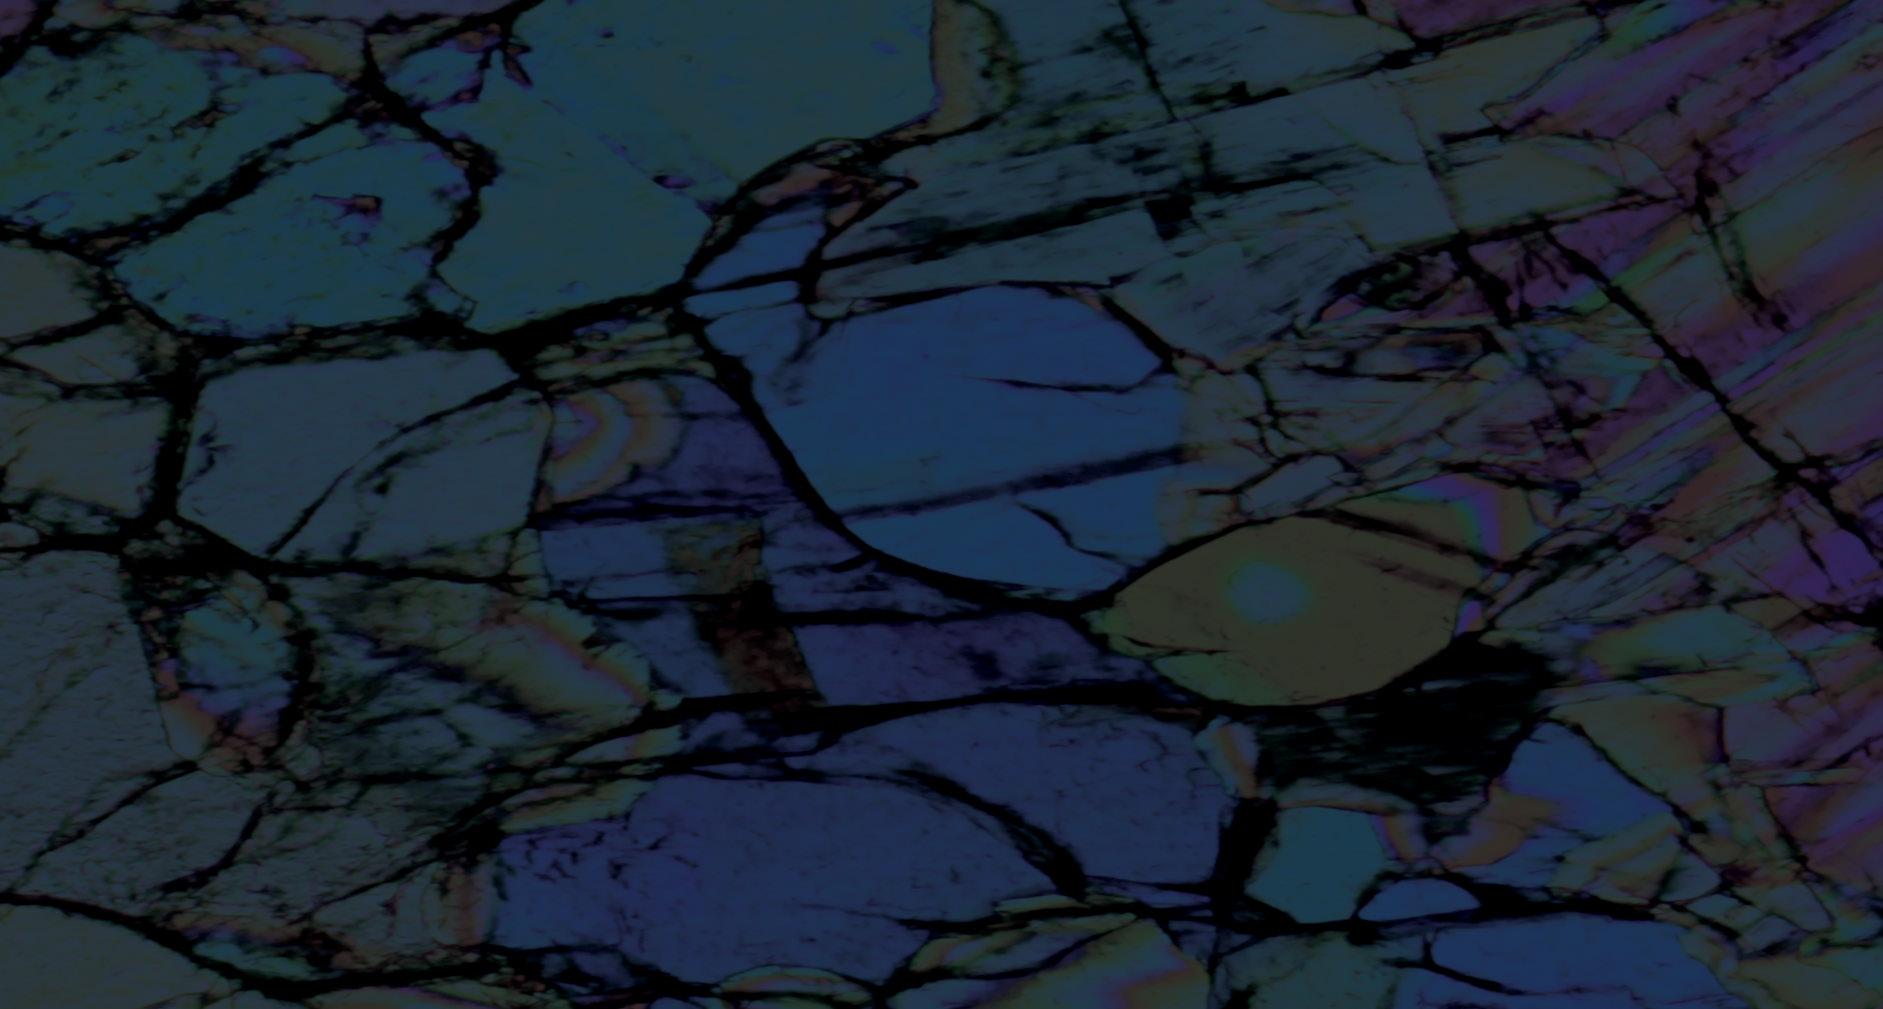

Age-dependent changes of alpha-Synuclein in the motor cortex

Alpha-synuclein (aSyn) is a protein found within the nerve cells of the brain. This protein controls the release of nerve signals and interacts with other nerve proteins to regulate neural function (Emamzadeh, 2016). Abnormal accumulations of aSyn lead to the brain disorder Parkinson’s Disease (PD) (Van Den Berge et al., 2021). PD, generally associated with older age, causes difficulties with movement, as well as behavioural and functional symptoms (Bloem, Okun and Klein, 2021). Despite its significance, the role of aSyn within the body and ageing process remains unclear. Here we used young (3-months) and older (12-months) mice to investigate how the expression of aSyn and 2 other nerve proteins Synapsin-1 (Syn1) and Homer1 (H1) change with age. We looked at the motor cortex area of the brain, as this has previously shown age-dependent change. We used staining, involving proteins tagged with a light-sensitive marker; and imaging, using a microscope, to visualise these proteins within our samples. We then used two programmes, ImageJ and MATLAB, to quantify protein expression and run statistical tests. We observed an increase in aSyn and a reduction in H1 expression in older samples. Subsequently we suggest that aging leads to a change in protein expression within the brain, which may be involved in brain disorders observed in older age.

Briefly, the methods involved in this project: adult (P120-390) PC57Bl/6 mice (n=8) were divided into two, sex matched, groups based on age. Brains were sagittally sliced into 40µm-thick sections using a frozen microtome and selected if they contained the motor cortex before primary and secondary antibodies (Figure 1a.) were applied for staining.

Figure 1. Experimental workflow, representative images and summary of findings. (a) Schematic illustration of experimental workflow.YA = young mice, 3 months old. LA = older mice, 12 months old. Primary antibodies: anti-alpha-Syn mouse, anti-Neun guineapig, anti-Homer 1 rabbit, antiSynapsin1 chicken Secondary antibodies: Goat anti-mouse ALEXA 405 fluorophore (AF 405), goat anti-guineapig ALEXA 488 fluorophore (AF 488), goat anti-rabbit ALEXA 568 fluorophore (AF 568), goat anti-chicken ALEXA 647 fluorophore (AF 647). Created in https://BioRender.com (b) Merged overview of a sagittal section showing the motor cortex. (c) Example of high-resolution images from the motor cortex, layer 2/3 expressing aSyn (red), H1 (blue), Syn1 (magenta) or NeuN (green). Merged image of all 4 channels. Scale bar: 15µm.

Imaging used the SP8 Lightning confocal microscope and DMI8 platform. Overview images required the 20x/0.4 dry objective lens, 1.00x digital zoom and high-magnification images required 40x/1.30 oilimmersion objective lens, 4.00x digital zoom. FIJI ImageJ and MATLAB were used to analyse molecular expressions. Using FIJI ImageJ, 12 ROIs were selected to measure the EGFP fluorescent signal intensity. A MATLAB code then analysed peaks in synaptic protein expression and colocalisation.

Here we find that the mean density of aSyn increased from YA to LA motor cortex, mirroring previous work demonstrating an accumulation of aSyn within the aged brain (Saito et al., 2003, Van Den Berge et al., 2021) (Figure 2a). Additionally, we demonstrate a significant reduction in the expression of H1 (Figure 2b), corroborating work showing agedependent changes within the dendritic spines and reduced capability for synaptic plasticity (Luo et al., 2012). Despite elevation in aSyn expression, we find no significant change in the expression of Syn1, suggesting this protein may be less vulnerable to age

Figure 2. Age-dependent changes in alpha-Synuclein, Homer1, and Synapsin1. Analysis of the motor cortex in YA and LA cohorts. Molecular expression is determined as a ratio between ROI and background signal intensity. Data are presented as mean expression/ colocalized puncta ± s.e.m, box plot or cumulative fraction distribution (a) Mean density (per ROI) of aSyn, Homer-1, and Syn1. aSyn (YA vs LA, P=0.0028), Homer-1 (YA vs LA, p=0.1920), Syn1 (YA vs LA, P=0.5316).Two variable t-test (t-test) was used to compare mean density of aSyn and Homer-1. Mann-Whitney U test was used to evaluate molecular expression of Syn1. (b) Box plot showing molecular expression of aSyn (YA vs LA, P=0.1629), Homer-1 (YA vs LA, p=0.0016), Syn1 (YA vs LA, P=0.1182. MannWhitney U test was used to evaluate molecular expression of aSyn and Homer-1. t-test was used to evaluate molecular expression of Syn1. (c) Mean density (per animal) of aSyn, Homer-1, and Syn1. aSyn (YA vs LA, P=0.2443), Homer-1 (YA vs LA, p=0.7625), Syn1 (YA vs LA, P=0.7456). t-test was used to compare mean density of all proteins. (d) Mean colocalised puncta. Colocalisation of aSyn, Homer-1 and Syn1 (YA vs LA, P=0.8854). t-test was used to compare the extent of colocalisation between cohorts. (e) Peak size plotted as a cumulative fraction distribution. aSyn (YA vs LA, P=5.7921e-04). Homer-1 (YA vs LA, P<0.0153). Syn1 (YA vs LA, P<1.5751e-23). *P < 0.05, **P<0.01, ***P < 0.001, NS not significant.

related change (Figure 2a, Figure 2c).

The co-expression of pre- and postsynaptic proteins was shown to be associated with the regulation of neurotransmission and neural plasticity (Radulescu et al., 2023). When evaluating the mean colocalised puncta in YA vs LA samples, we find no change in the number of colocalised puncta (Figure 2d). Our findings suggest that interactions between the preand postsynaptic remain stable through ageing to maintain their connection and neurotransmission.